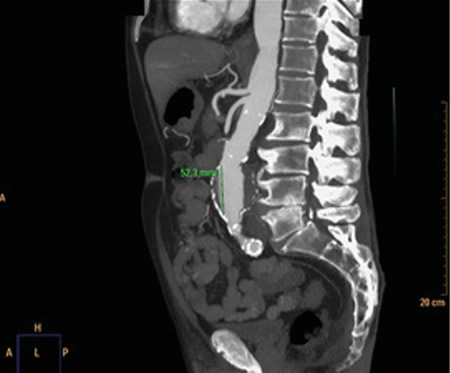

Figura 1

La rotura de aneurisma de aorta supone el síntoma principal en hasta un 25 % de los casos de la patología de aneurisma de aorta, que constituye una entidad potencialmente mortal. También puede aparecer con menor prevalencia como lumbalgia, coxalgia e, incluso, gonalgia, no comentándolo como dolor vertebral o neuropático, sino como irritación a nivel de psoas ilíaco como primera sintomatología.

Se estima que solo en un 50 % de los casos aparece la triada clásica del aneurisma, por lo que es necesario tener un alto nivel de alerta para sospecharlo, ya que la hipovolemia puede estar contenida por un hematoma peritoneal.